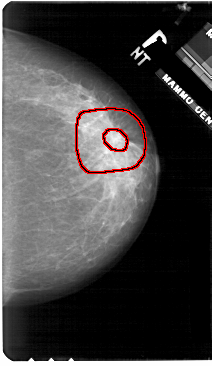

A_1906_1.RIGHT_MLO

RIGHT_MLO LINES 5491 PIXELS_PER_LINE 3541 BITS_PER_PIXEL 12 RESOLUTION 43.5 OVERLAY

FILE: A_1906_1.RIGHT_MLO.OVERLAY

TOTAL_ABNORMALITIES 1

ABNORMALITY 1

LESION_TYPE MASS SHAPE ARCHITECTURAL_DISTORTION MARGINS SPICULATED

ASSESSMENT 5

SUBTLETY 4

PATHOLOGY MALIGNANT

TOTAL_OUTLINES 2

BOUNDARY

CORE